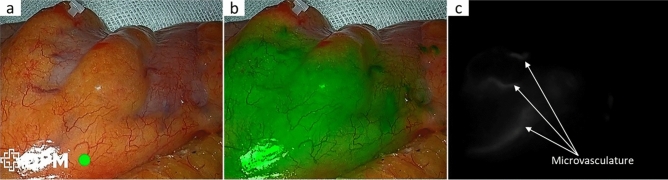

Background: Neoadjuvant chemoradiotherapy (nCRT) is key for low rectal cancer but raises the risk of anastomotic leakage (AL). This study examines how fluorescence laparoscopic (FL) surgery reduces AL after intersphincteric resection (ISR), especially in nCRT patients.

Methods: This real-world multicenter cohort study included 533 patients undergoing laparoscopic ISR for ultra-low rectal adenocarcinoma from January 2012 to July 2023. Patients were categorized into FL and non-FL groups. Propensity score matching (PSM) was used at a 1:2 ratio to adjust for baseline differences. The primary endpoint was the incidence of AL within 6 months postoperatively. Secondary endpoints included anastomotic site perfusion, intraoperative blood loss, lymph node retrieval, perioperative complications, and postoperative recovery metrics. Subgroup analyses were conducted on the basis of nCRT status.

Conclusions: Fluorescence-guided laparoscopic surgery reduces anastomotic leakage and improves outcomes in low rectal cancer, especially after chemoradiotherapy, by enhancing surgical precision and recovery.